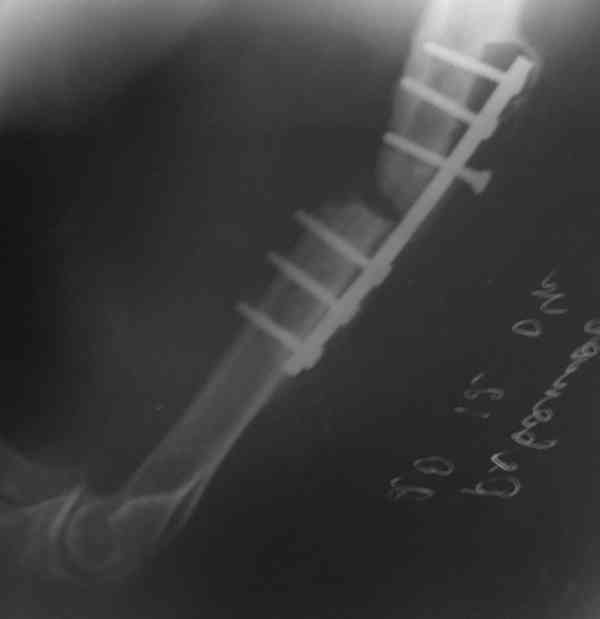

Штифт - отвисание проксимального отдела - накостный остеосинтез, нагноение, АФВ с ревизиями раны, опять пластина и снова нестабильность. Была удалена пластина и выполнен БИОС штифтом ChM (ДЕОСТ). Через 2 нед. пациент сел за руль и вышел на работу. Причем так и работает до сих пор уже 1,5 года, хотя полного сращения мы вроде бы не достигли ( снимки пришлю позже) - пациент не приходил на осмотры, общался только по телефону.

Мы бы предложили БИОС ретроградно (хотя это не принципиально, можно и сверху). Учитывая,что ложняк "болтающияся", больших трудностей с закрытым вскрытием канала (в зоне ложного сустава) быть не должно. Конечно нужен инструмент: сначала длинная (350-400 мм) острая спица (шило)диаметром 4-5 мм., затем гибкие развертки до 8-9 мм и соответствующий массивный штифт...